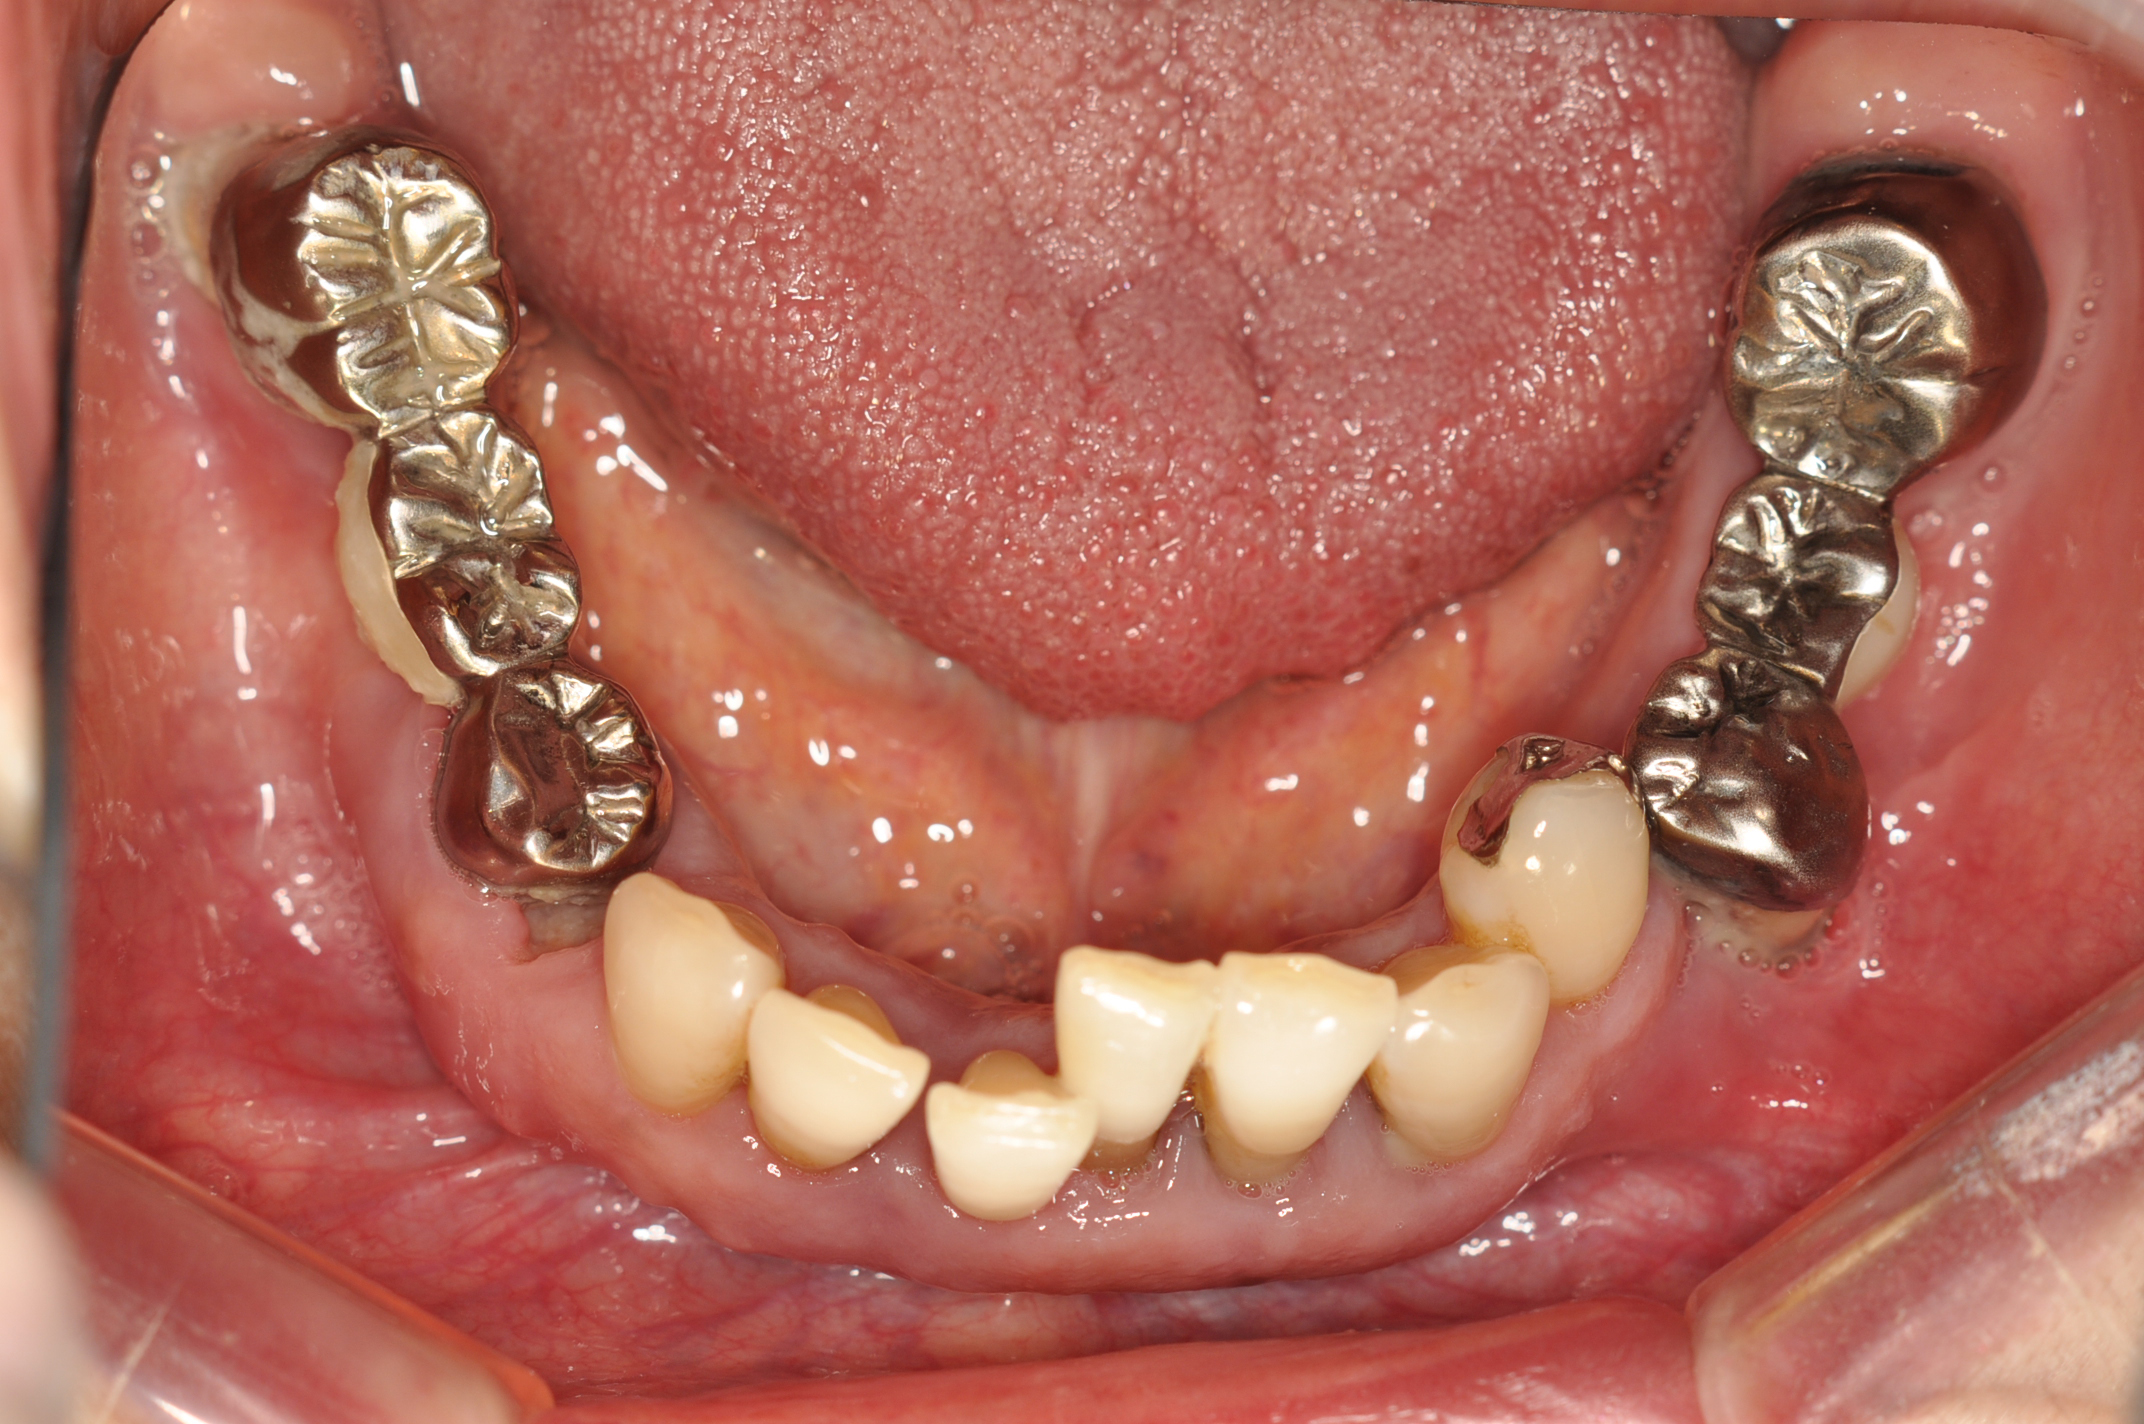

50代女性 部分義歯で対応した重度歯周病症例

娘さんがHPで安藤歯科を探していただいたそうです。義歯が入っているように見えない事が治療条件でした。

試適時の咬みわせチェックの写真です。装着時も咬合器にリマウントしてチェックします。

FDI表記 23 25 26 35 37 42 44 45 47